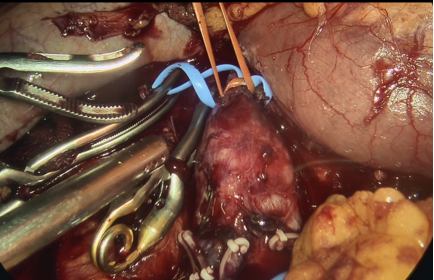

图为:血管吊带重新阻断下腔静脉近心端,仍阻断不住下腔静脉喷血。

图为:及时中转开腹,探查发现下腔静脉左后外侧腰静脉未阻断,阻断后不再喷血